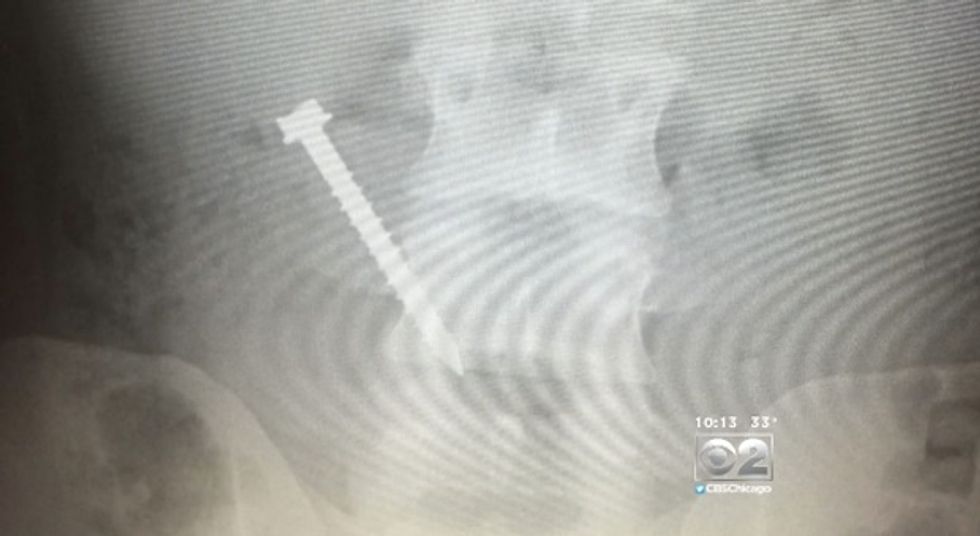

An investigation by WBBM-TV in Chicago has uncovered that some inmates held in Cook County Jail are actually eating parts of the jail. This very bizarre habit is also expensive, potentially costing the state of Illinois tens of millions of dollars in surgeries, aftercare and manpower costs.

Each case of an inmate ingesting pieces of metal means a trip out of the jail to a local hospital for evaluation, x-rays and possibly surgery. The costs are compounded because two guards must accompany each inmate.

According to the report, Lamont Cathey, is just one inmate with the metal-munching habit. Cathey has reportedly needed 19 to 20 surgeries, costing Illinois taxpayers more than $1 million.